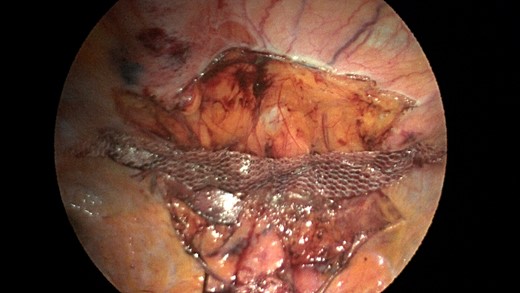

A sleeve of Parietex composite mesh cut to act as a suture bolster under the diaphragm edge to prevent the sutures from pulling through the diaphragm muscle.

Additionally, another Pariatex composite mesh was then trimmed to 12 cm in width by 9 cm, soaked in vancomycin with local anesthetic and then placed into the abdominal cavity. It was positioned over the area of the repair and fixed into place with absorbable tacks around its caudad edge and centrally. Along the cephalad edge it was fixed with a running V-lock absorbable suture to the diaphragm. Fibrin glue was placed along this same edge (Fig. 7). The ports were removed and incisions were closed.

Completed view of the second main mesh piece placed with overlap of the defect and tack fixation in place.

CT scan is obtained for a specific diagnoses of Morgagni hernia in order to strategize your surgical approach. Minimally invasive laparoscopic techniques have become a popular option in the 21st century due to reduced intraoperative morbidity and quicker recovery rates [9]. Our case was unique in that the novel use of a sleeve of composite mesh was used as a bolster for the Ethibond suture as opposed to felt pledgets so the suture would not pull through the diaphragm. This sleeve of mesh was separate from the main mesh that was used to cover the overall repair (see pictures).